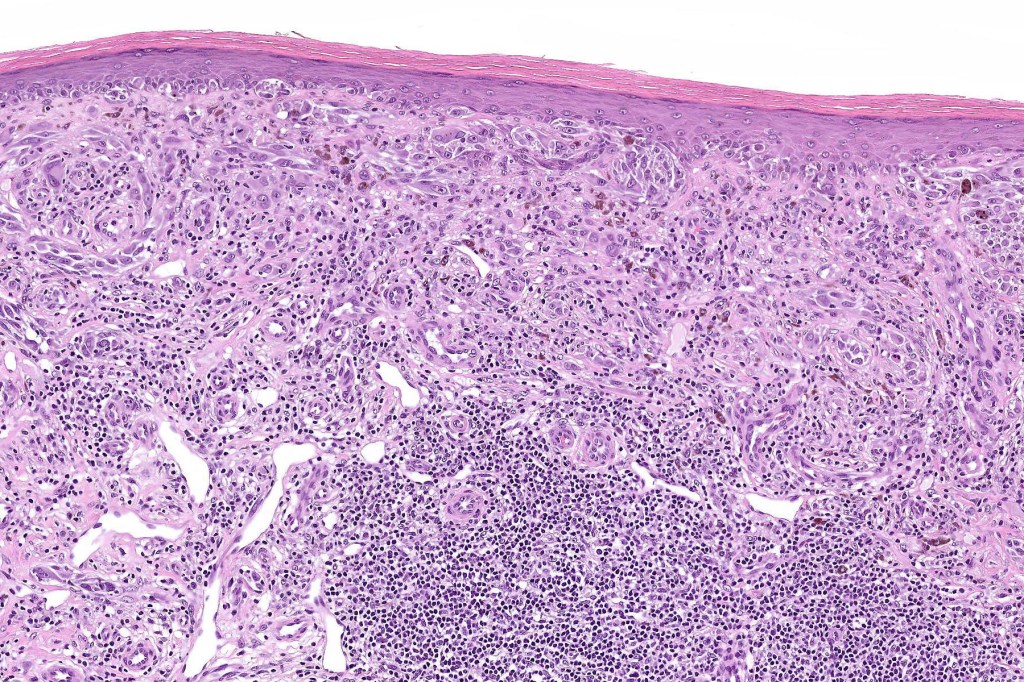

Histological features

•>5-10 mm

•Involve deep dermis or subcutis

•Asymmetrical, poorly circumscribed

•May show effacement/consumption of epidermis or ulceration

•Peripheral Pagetoid spread

•Large nodules which often show impaired maturation

•Loss of gradient with HMB45 and Ki67

•>20% Ki67 expression

•TERT promoter & PTEN mutations

•DNA copy-number variations